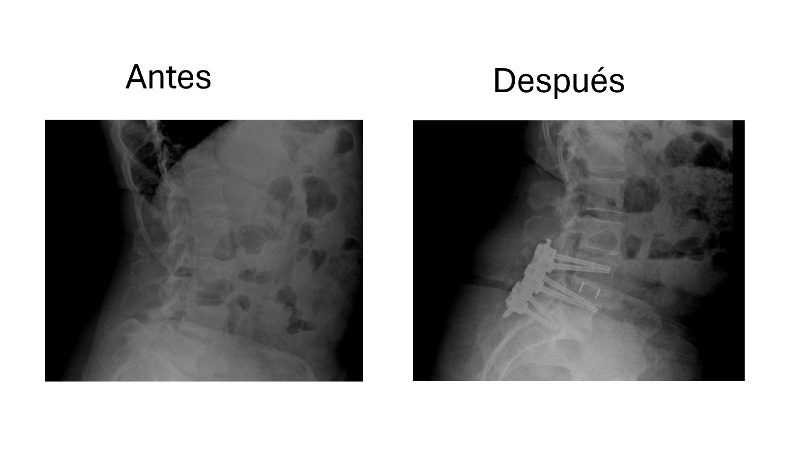

Abordaje cervical anterior con colocación de caja intersomatica C5-C6

Después de años con dolor intenso y limitación en el cuello, me realizaron un abordaje cervical anterior con colocación de caja intersomática en C5-C6. La recuperación fue rápida y el alivio fue casi inmediato. Volví a mis actividades sin molestias. Estoy muy agradecido con el equipo médico.